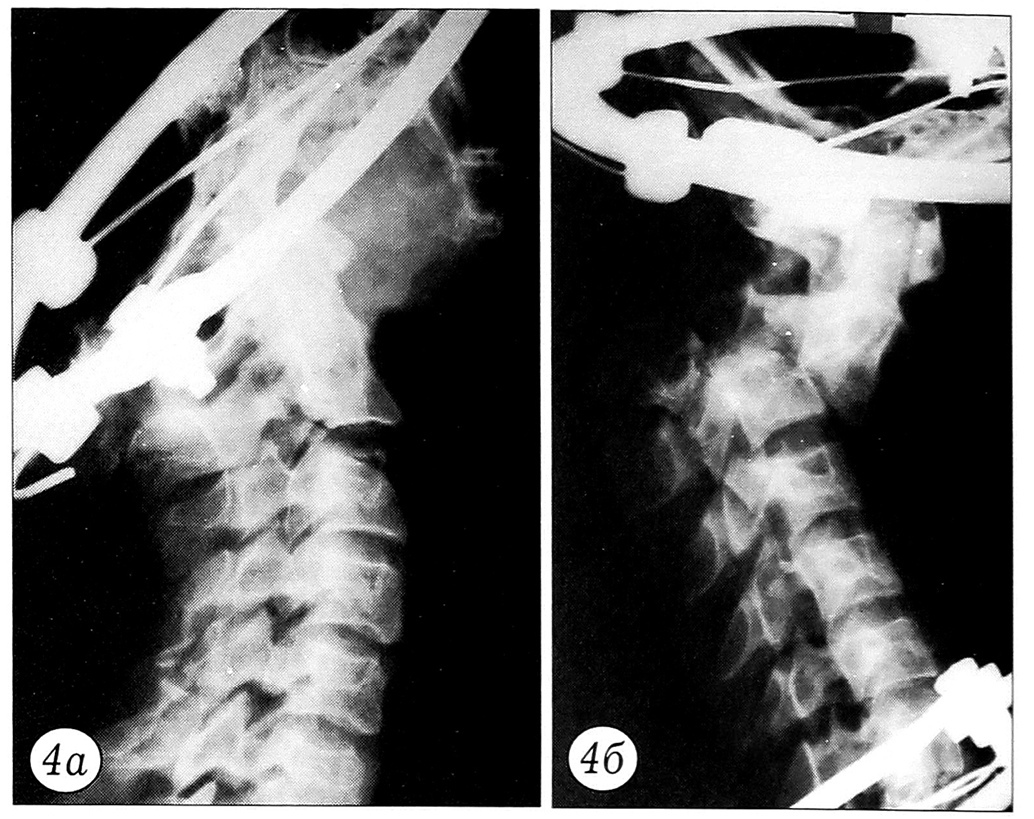

Результаты нагрузочного теста документировались графически. По оси ординат регистрировалось усилие в ньютонах, по оси абцисс — степень смещения позвонков в миллиметрах (рис. 2). При этом основное внимание уделялось величине нагрузки, при которой происходило наибольшее смещение позвонков. До и после нагрузочного теста производилась рентгенография блоков (рис. 3~5).

Рис. 5. Перелом Джефферсона до (а) и после (б) нагрузочного теста. На рентгенограмме в боковой проекции после нагрузки видно расширение щели сустава Крювелье.